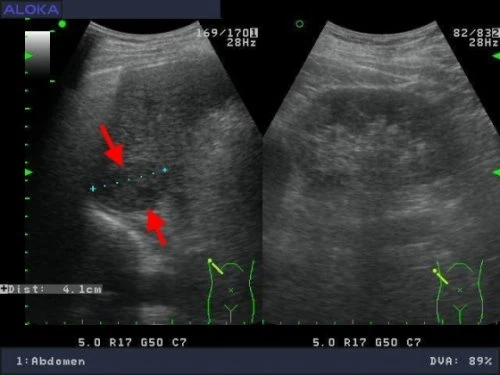

深部肝癌

![]() 8.4公分肝癌 1/2 更多的影像請連結:http://www.doctor.tw/gallery/index.php?type_id=9 |